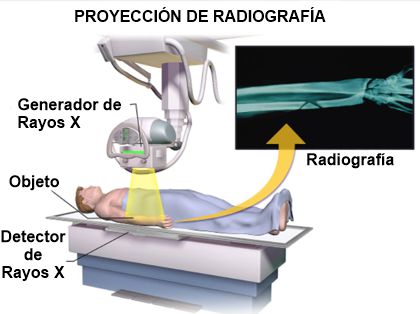

¿Qué son los Rayos X?

Los Rayos X son un tipo de radiación llamada ondas electromagnéticas. Estos son capaces de mostrar el interior del cuerpo en distintos tonos de blanco y negro.

Su uso más frecuente es para ver fracturas aunque también tiene otros usos como por ejemplo detectar neumonías o el cáncer de mama.